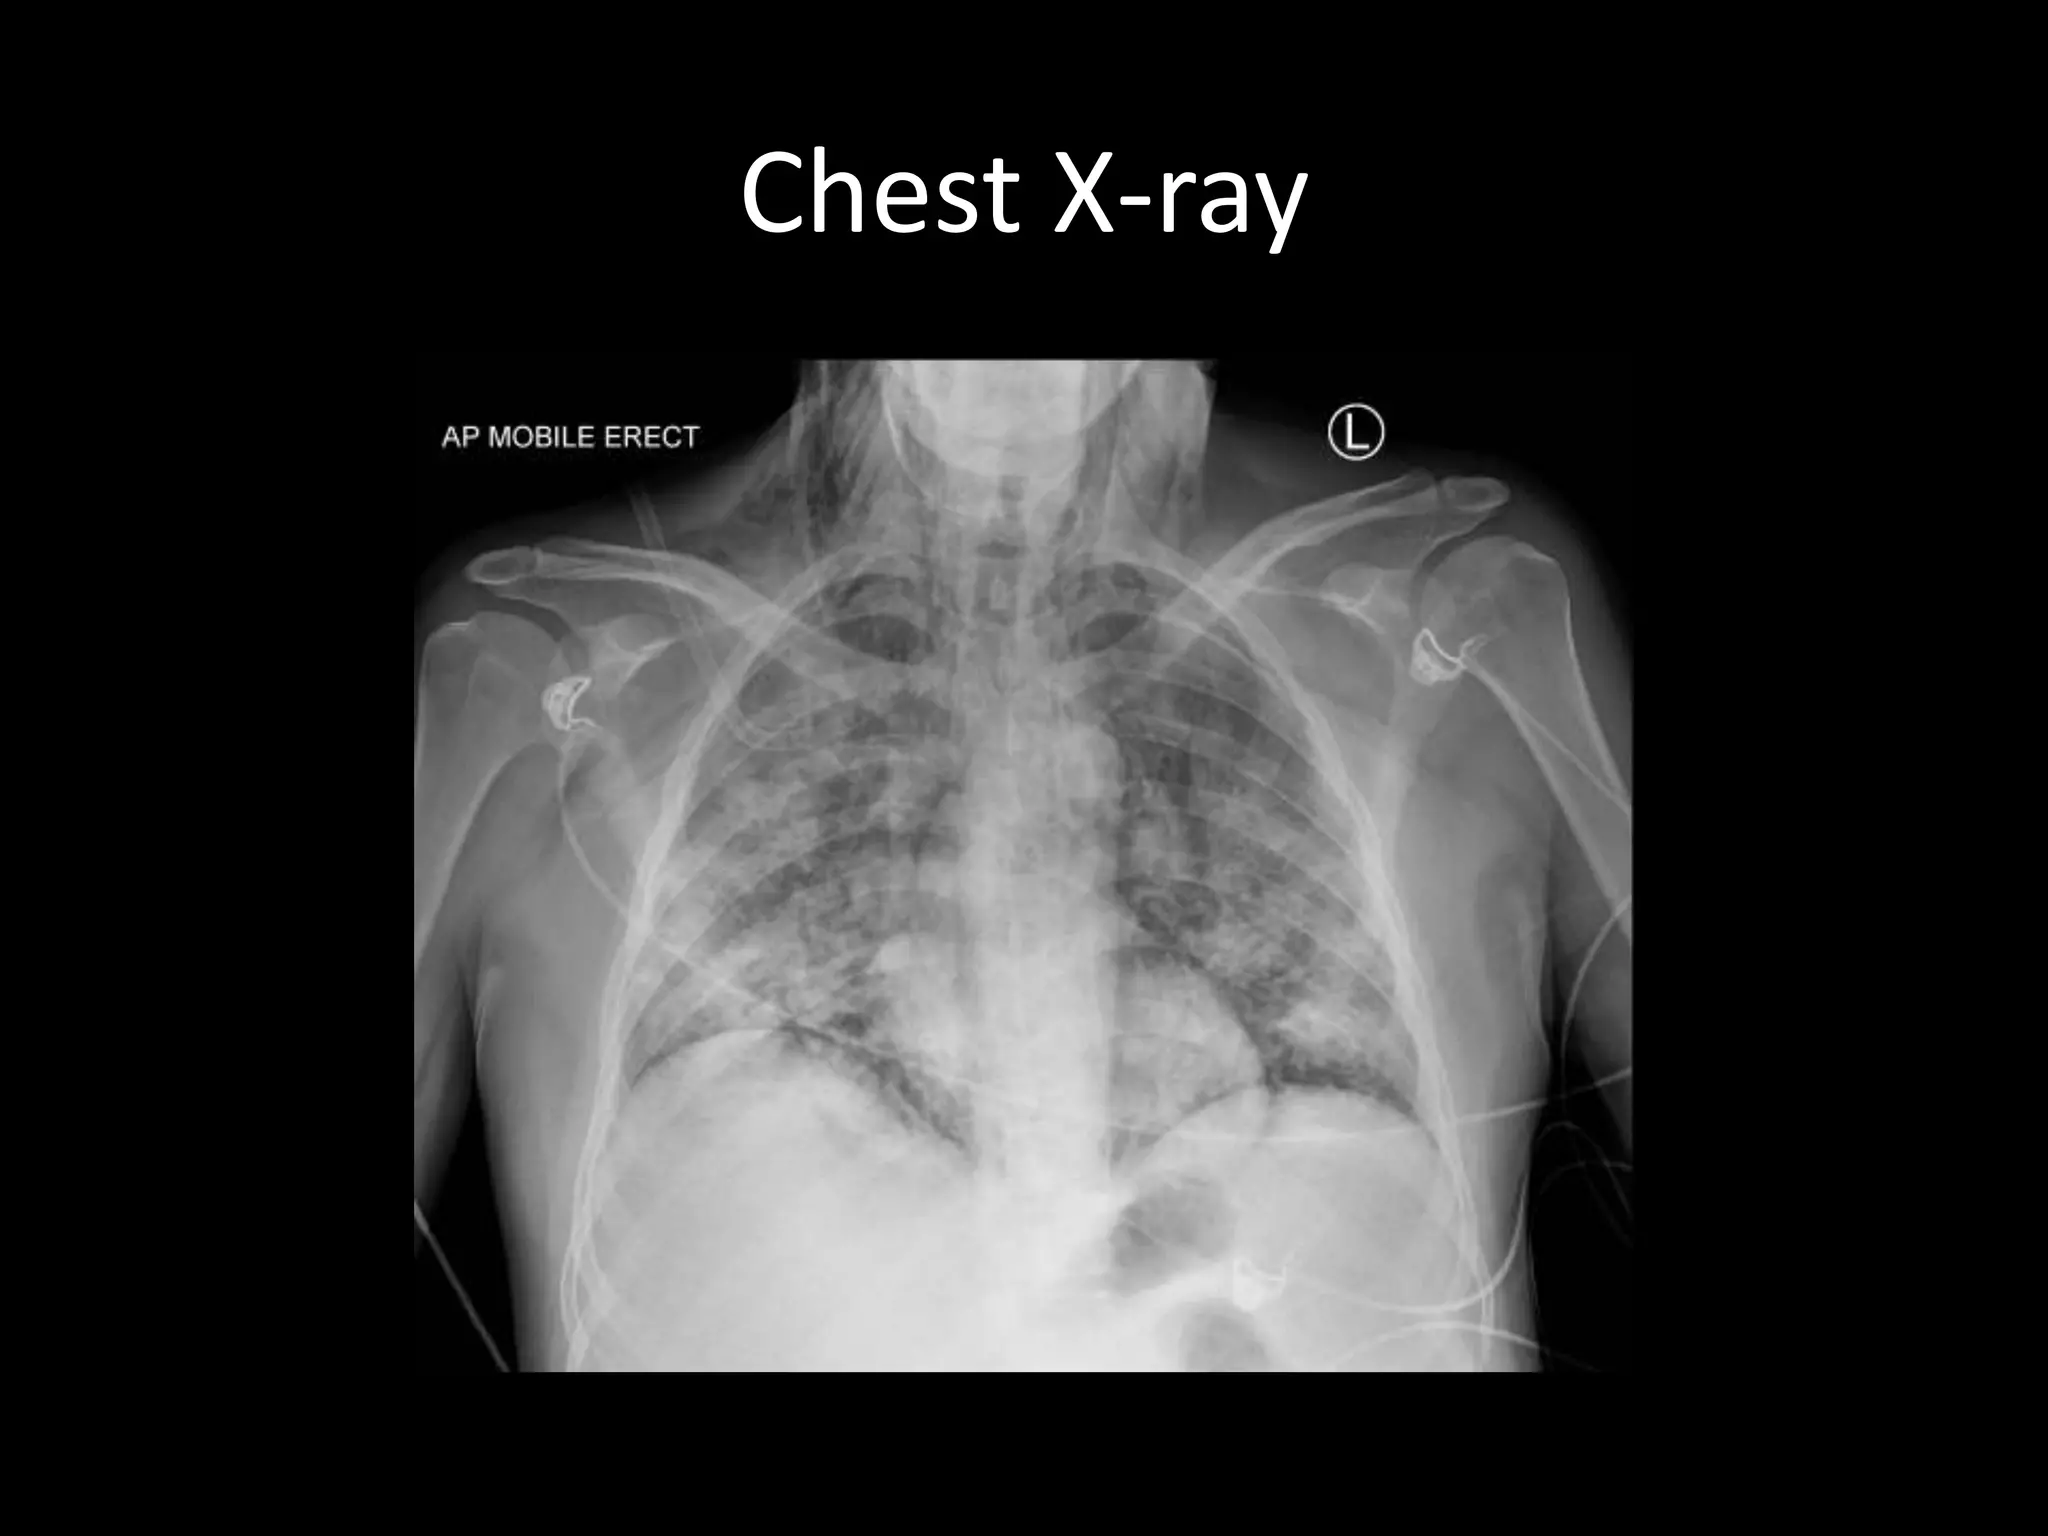

Chest X-ray

Ultrasound Findings

• Surgical emphysema

• Small pneumothorax

• Widespread patchy consolidation

• H1N1 pneumonitis